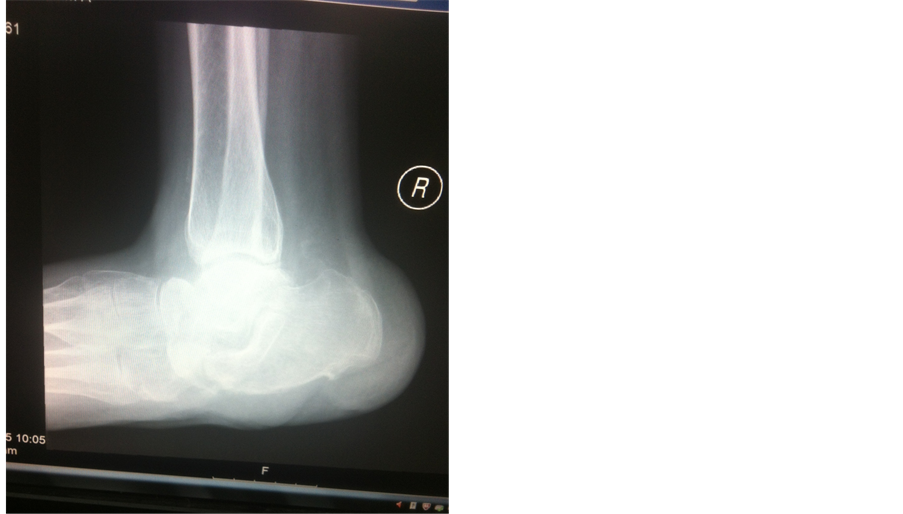

Figure 8. Charcot foot.

Figure 9. Charcot foot.

Figure 10. Rocker bottom foot deformity.

Figure 11. Hind foot deformity.

Figure 12. Hind foot deformity.

Figure 13. Calcaneo-taler angle deformity.

Co-morbidities had a role in development of Charcot disease Associated co-morbidities were obesity in 10.9%, hypertension in 83.8%, dyslipidemia in 31.3%, hypothyroidism in 14.1%, immunosuppression in 3.1% of cases, arrhythmia in 3.1% and anemia in 84.4%. Most associated co-morbidity was hypertension. Charcot arthropathy was in 28.1% of cases and forefoot was involved in 65.5%, midfoot in 4.7% and hindfoot/ankle in 21.9%. Forefoot involvement was found in majority of our patients. X-rays showed subluxation in 40.6%, dislocation in 54.7%, disorganized foot joints in 42.2%, bone resorption in 23.4%, osteomyelitis in 14.1%, fractures in 50%, joint collapse in s39.15 and destruction of articular surfaces in 37.5%. Common pathology in our patients were subluxation and dislocation in forfoot joints.

Mean age of our patient was 61.4 years which is near similar to studies of Sanders et al. where it was mid fiftees [12] and 63 years in study of Min et al. [16] . Charcot foot disease is commonly found in elder population. In our study majority of patients were males 81.2%, and females 18.8% while Min et al. reported males 97.1% [16] . This again confirms the fact that diabetic foot disease is a disease of middle age and Charcot neuroarthropathy develops in long standing diabetic foot disease. Males are commonly involved in Charcot disease as they are commonly do the manual work and spend long time in doing physical work related to their profession. Twenty five percent patients complained of foot pain in our study while Baglioni, Botek, and Petrova et al. reported pain in less than 50% of cases [17] - [19] . Since patients with Charcot neuroarthropathy have neuropathy so less number of our patient reported pain. 62.5% of our patients had diabetes for more than 10 years which is similar to studies of Leung et al. and Samann et al. [4] [20] . X-rays were used to diagnose bony changes in Charcot patients. Initial X-rays were normal and patients had only soft tissue deformity. 28.1% of diabetic patients had Charcot foot disease in our patients which is quite high percentage. Forefoot was involved in majority of our patients 65% followed by hind foot and midfoot. Offloading was non operative management and commonly it was foot wear. The gold standard of off-loading is the total contact cast [11] [21] . Arthrodesis of joints is another option for treatment. Surgery in the form of debridement and amputation was offered in majority of our patients. Majority had toe amputation followed by below knee amputation.